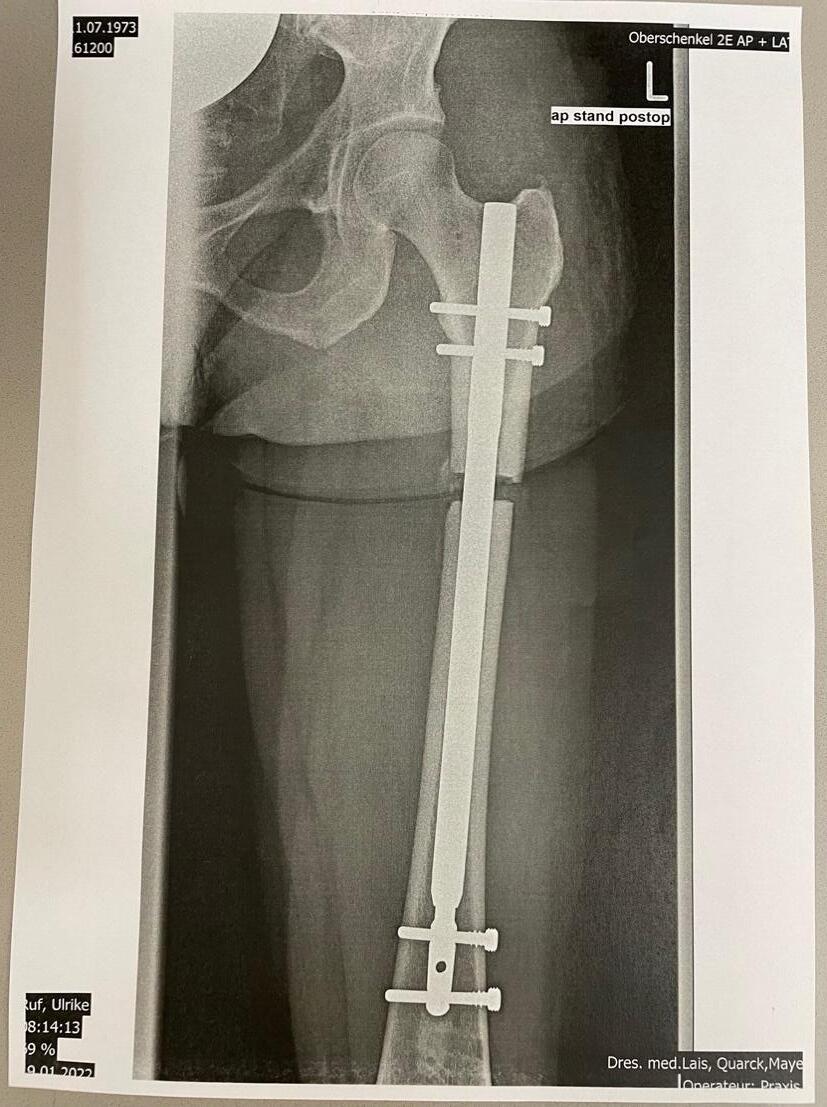

- Medical history, physical examination, photo documentation, X-rays of the long bone and discussion of the X-rays. Personal photo simulation of an extension, creation of a preliminary operation plan with selection of an individually-optimal implant. Information about therapy procedures, rehabilitation options, accommodation options, treatment and any additional costs.

- Every six weeks an X-ray should be taken and sent to our institute. At the end of the extension phase, you will see our specialists again as an outpatient. If there are still functional deficits at this point, the physiotherapy plan is individually adjusted.

Fully implantable intramedullary distraction nails:

In order to use the characteristics of callus distraction without having to accept the disadvantages of external fixators, fully implantable intramedullary distraction nails have been developed since the 1980s. Conventional intramedullary nails made of steel or titanium have been used in the treatment of fractures for over 50 years. All distraction intramedullary nails available on the world market today are based on such intramedullary nails. These have sophisticated inner workings that allow them to be distracted.

The Albizzia® is a mechanical distraction nail developed by Drs. Guichet and Grammont in which lengthening is achieved by rotating the affected leg back and forth by 20 degrees until an audible click is heard. The nail used by Dr. med. A. Becker - the Betzbone®, is a further development or better said, a modification and improvement of the Albizzia®. The material of the nail is stronger and the interlocking in the bone has been better adapted to the anatomy of the bone. The Betzbone® has the highest stability and extension capacity (up to 12 cm) of all intramedullary distraction nails currently on the market. The high stability allows an early full-bearing load and unrestricted physiotherapy directly after the operation. It also allows a reliable feed with secure function and requires only a few clinical and

X-ray checks. The initial activation of the extension mechanism requires sensitive guidance from the surgeon.

The exact analysis of the leg geometry is based on X-rays of the whole leg and, if necessary, computer tomography. Based on this diagnostic imaging, the various treatment options are discussed with the patient and the operation is planned. Due to blood-saving, minimally invasive surgical techniques, blood transfusions are not necessary. The operation takes place under general anesthesia and lasts, with simultaneous application, several hours. The nail is inserted through a single small incision after the medullary cavity has been prepared. Long tubular bones have a solid, compact outer layer of bone. The inside consists of bone trabeculae near the joint, in the shaft area there is the marrow cavity for the bone marrow. These bone trabeculae enable a stable lightweight construction.

After drilling, the nail

During the preparation of the medullary canal to implant the lengthening nail, a small hollow needle, which is screwed into the lower part of the bone and which is later removed, prevents the pressure in the medullary canal from increasing too much thereby reducing the risk of bone meal and bone marrow washing into the bloodstream.

The artificial growth plate is done by using a special internal saw at the inside of the bone, i.e., via the same cavity into which the nail is then inserted. Usually, it is created from the outside with the help of bone saws or bone chisels, with the soft tissues at the site of the transection also having to be injured. This is what can be avoided by using an internal saw.

A single dose of antibiotics is administered intraoperatively to prevent infection. On the day of the operation, latest on the following day, the patient gets up for the first-time using support.

In the following post-operative rest phase, there are only isolated lengthening impulses.

After 5-7 days, the actual lengthening process begins with a distraction speed of up to 1 mm per day on the thigh and up to 0.5 mm on the lower leg. Careful and regular physiotherapy is essential for this process, possibly supported by individually adapted pain therapy.